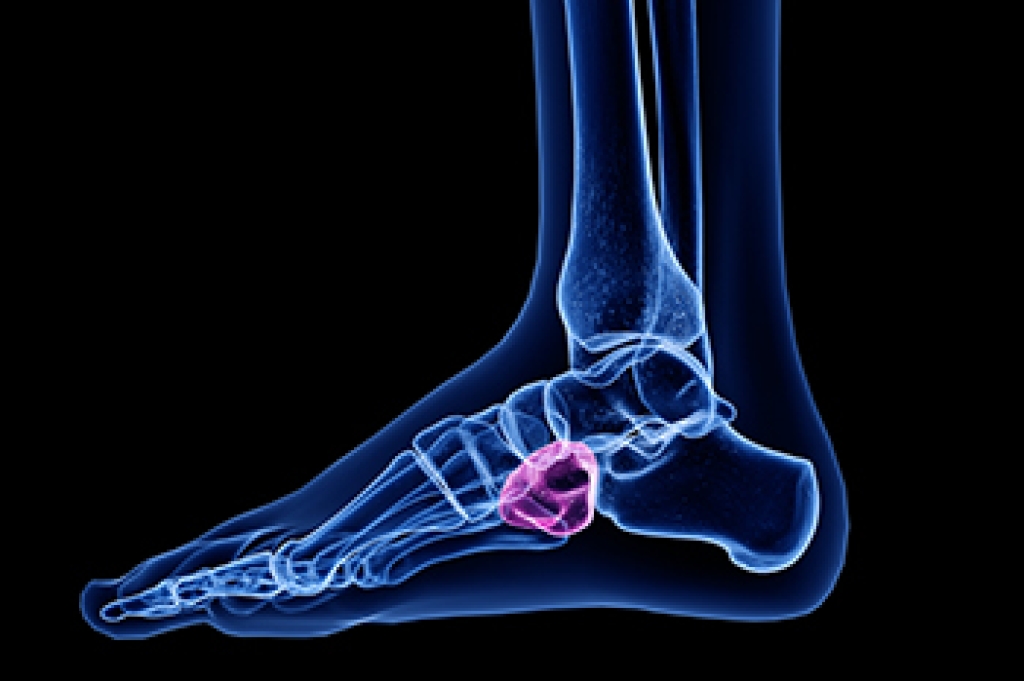

The most common injuries that occur in sporting activities include:

- Achilles Tendonitis

- Achilles Tendon Rupture

- Ankle Sprains

- Broken Foot

- Plantar Fasciitis

- Stress Fractures

- Turf Toe